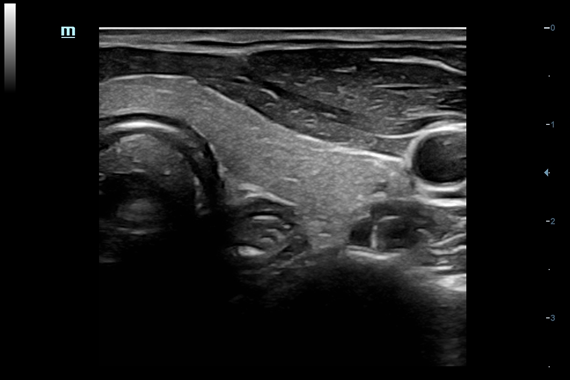

• Smart FLC™ - режим автоматического оконтуривания, подсчета и определения размеров фолликулов из объемного изображения (необходим модуль 4D)

• Gynecology package - предустановленные параметры, аннотации, маркеры, программы измерений для гинекологии

• IVF package - предустановленные параметры, аннотации, маркеры, программы измерений и отчеты для ЭКО (требуется наличие пакета программ измерений и расчетов для гинекологии)